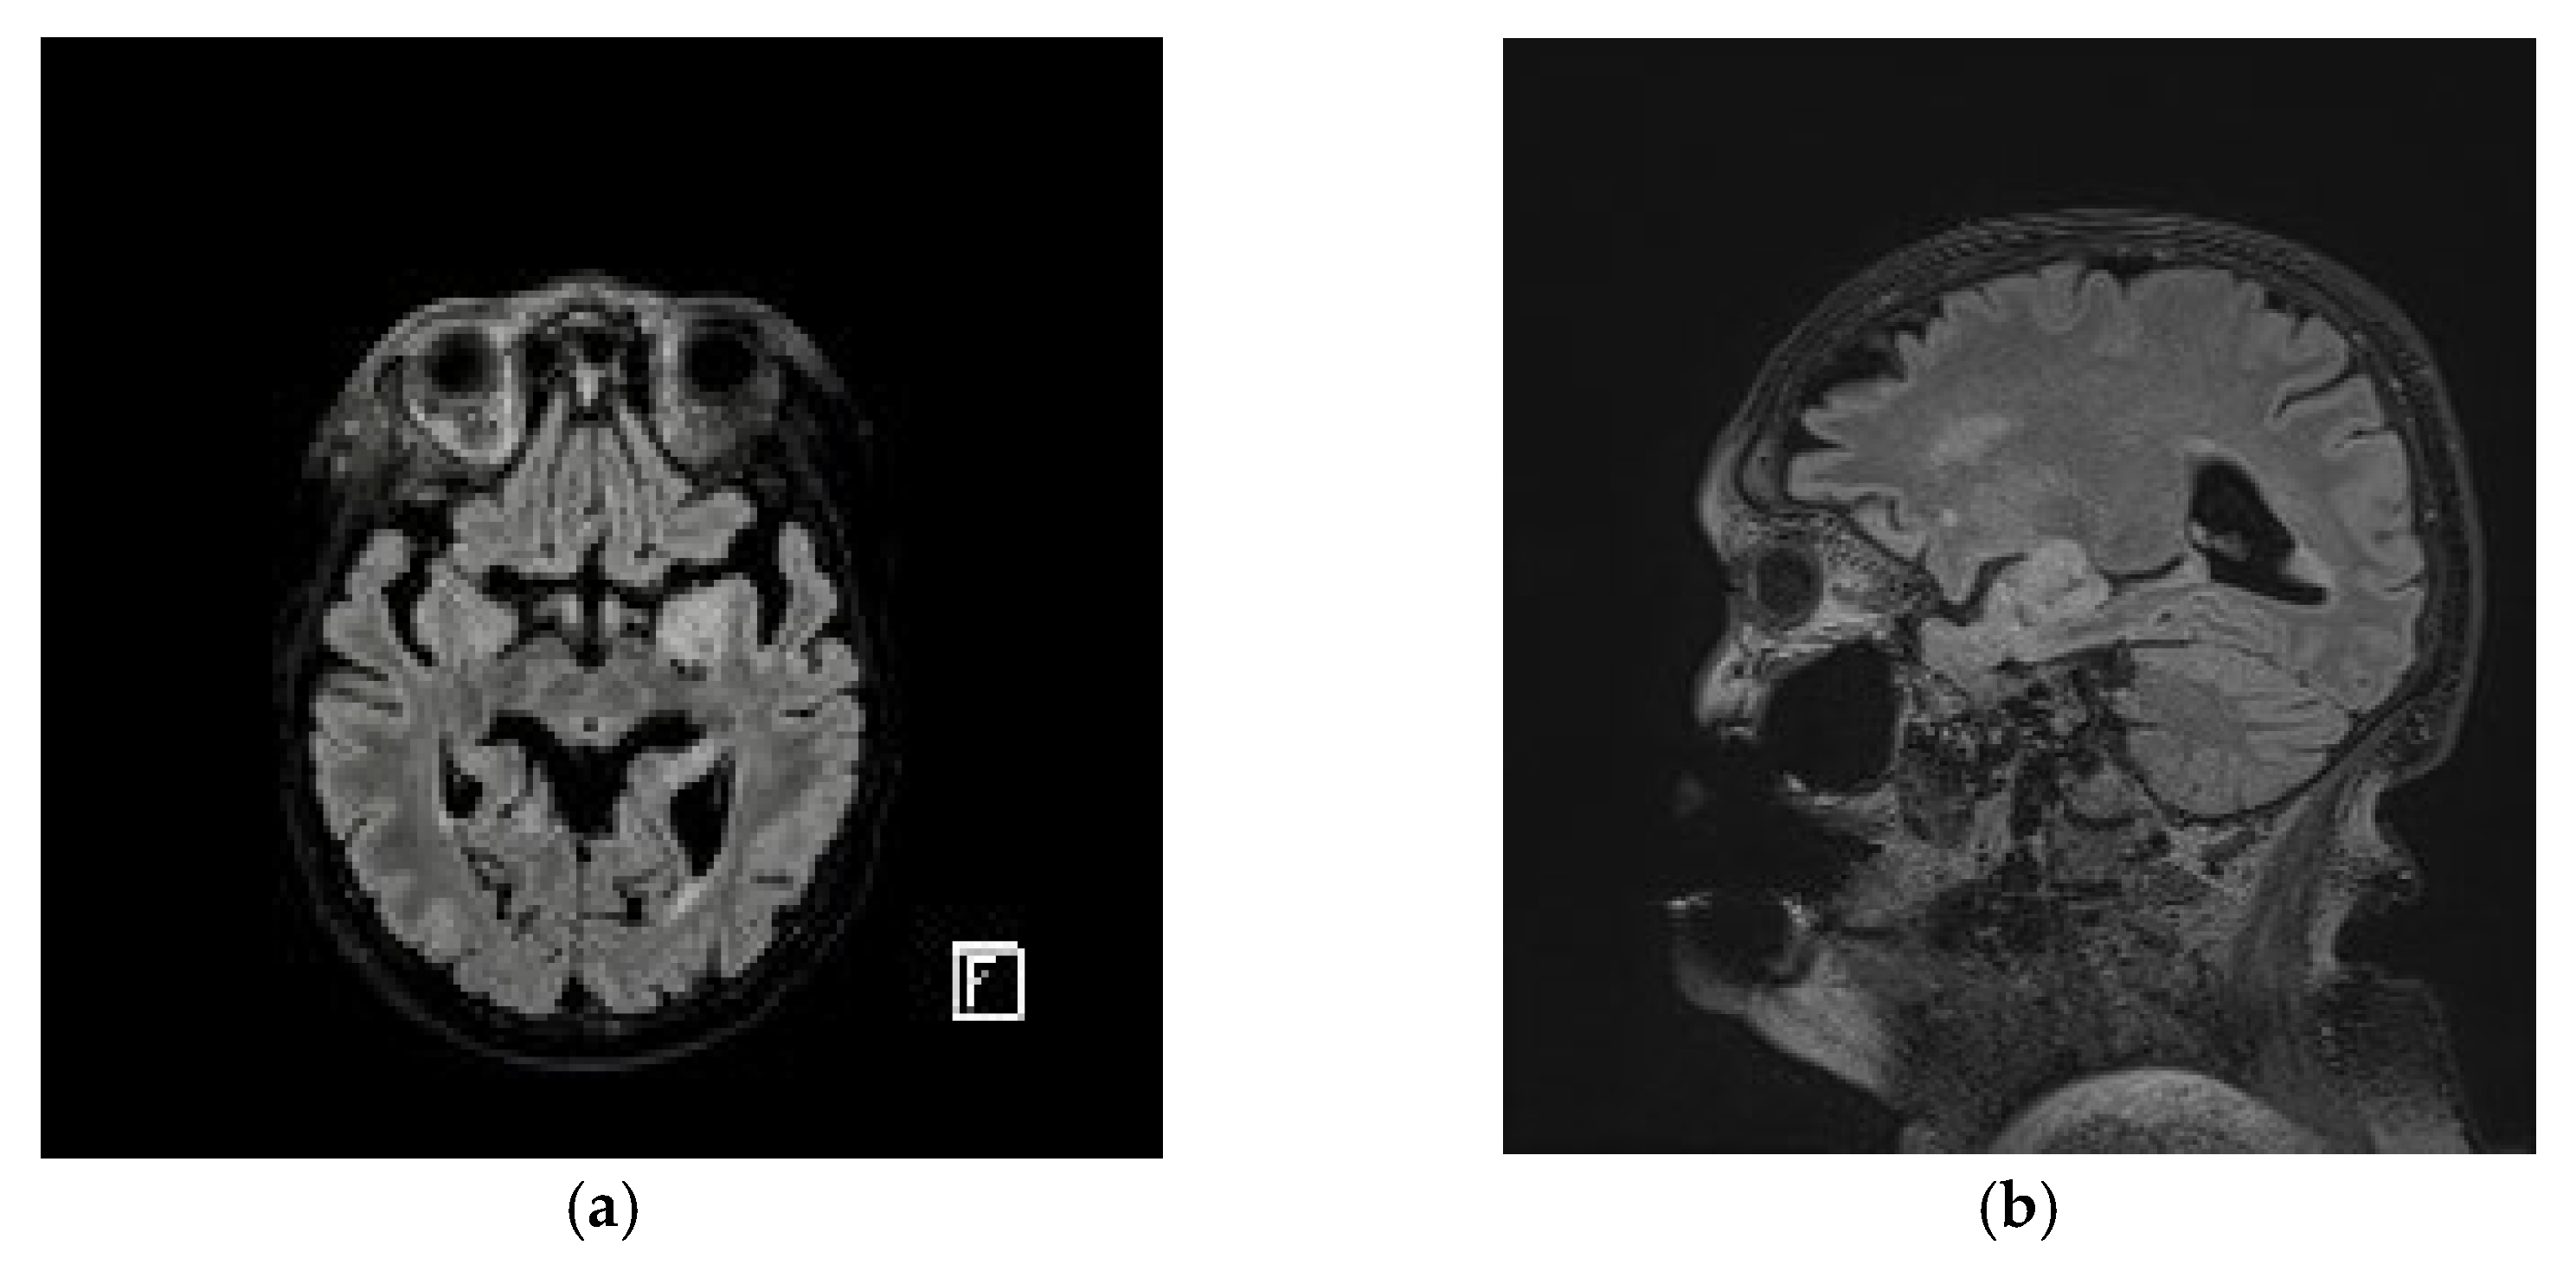

2. Case Presentation

3. Results